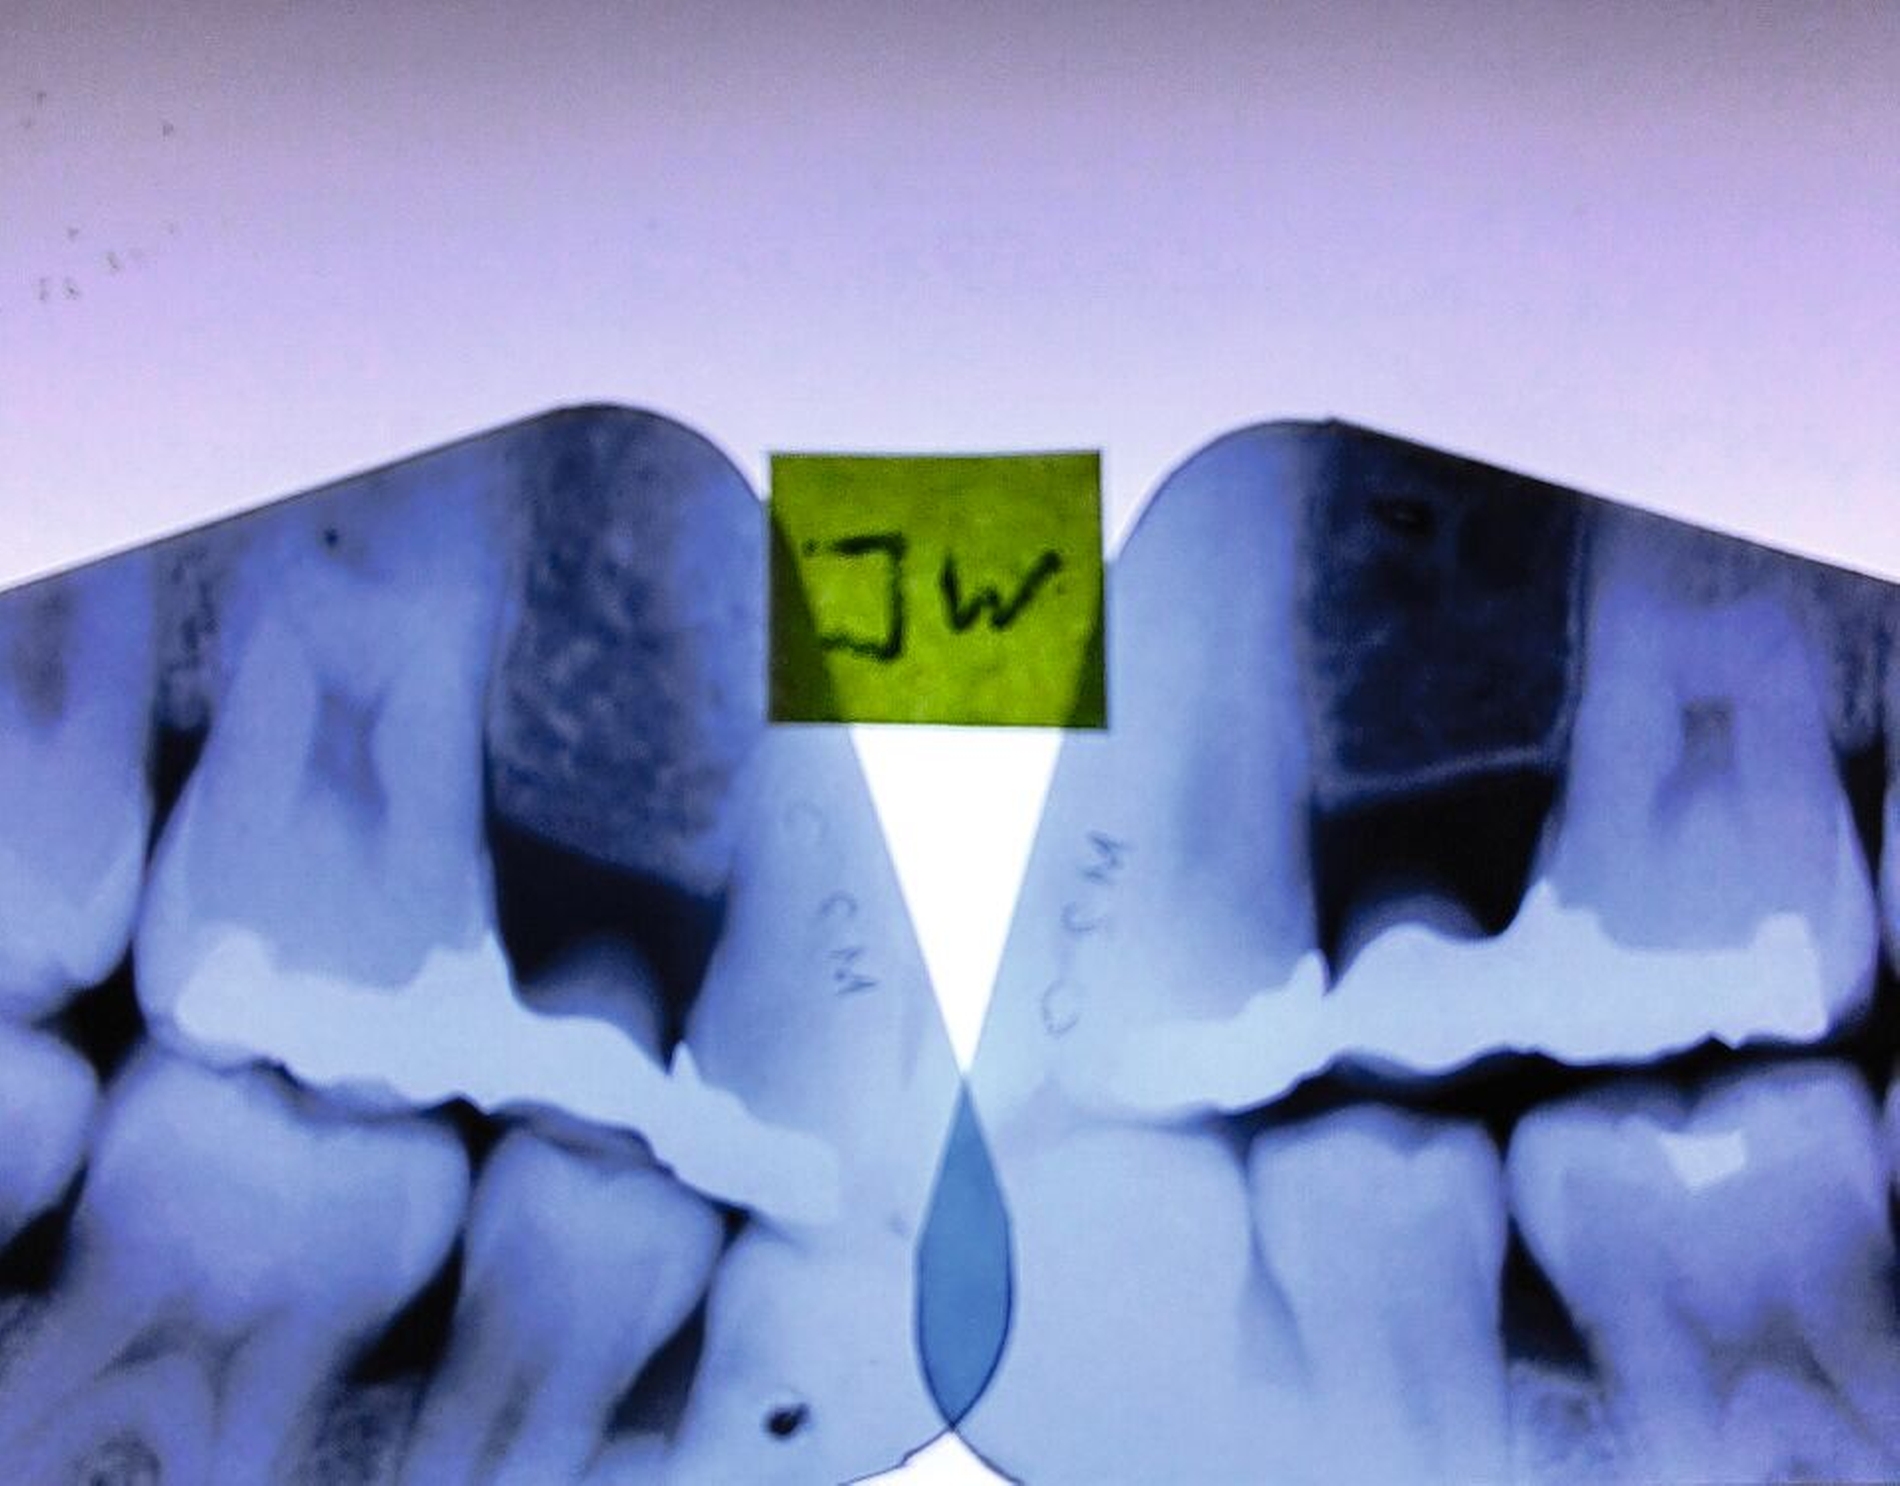

In den Abbildungen werden drei Fallbeispiele vorgestellt, bei denen alle Brücken noch in situ sind: